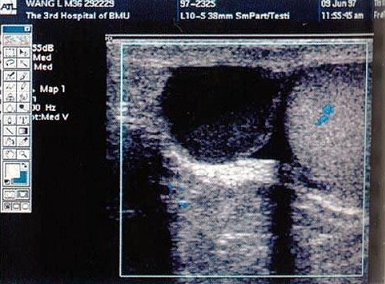

29、单项选择题

某患者五日前阴囊碰伤,现感右侧阴囊不适,超声声像图如下,最可能的诊断为()

A.睾丸血肿

B.精原细胞瘤

C.睾丸炎

D.睾丸扭转

E.睾丸脓肿